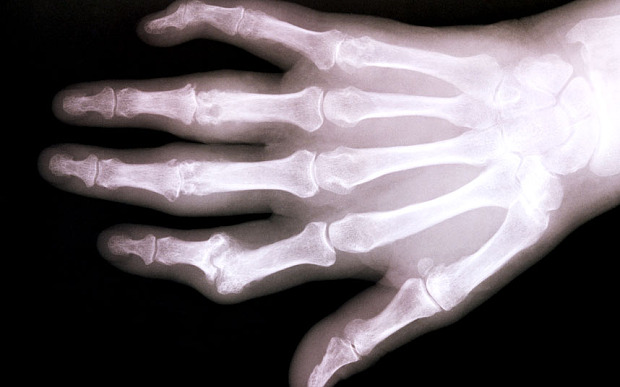

Xương có thể được tái sinh để hỗ trợ cho người bị bệnh loãng xương. |